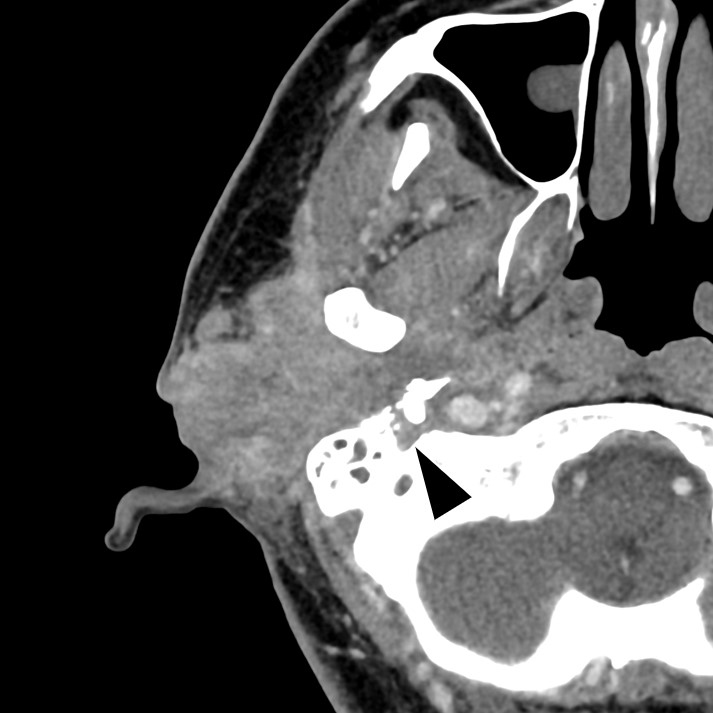

A Case of the Monocle Sign in Facial Nerve Palsy Caused by External Auditory Canal Cancer on 18F-fluorodeoxyglucose-positron Emission Tomography/Computed Tomography.